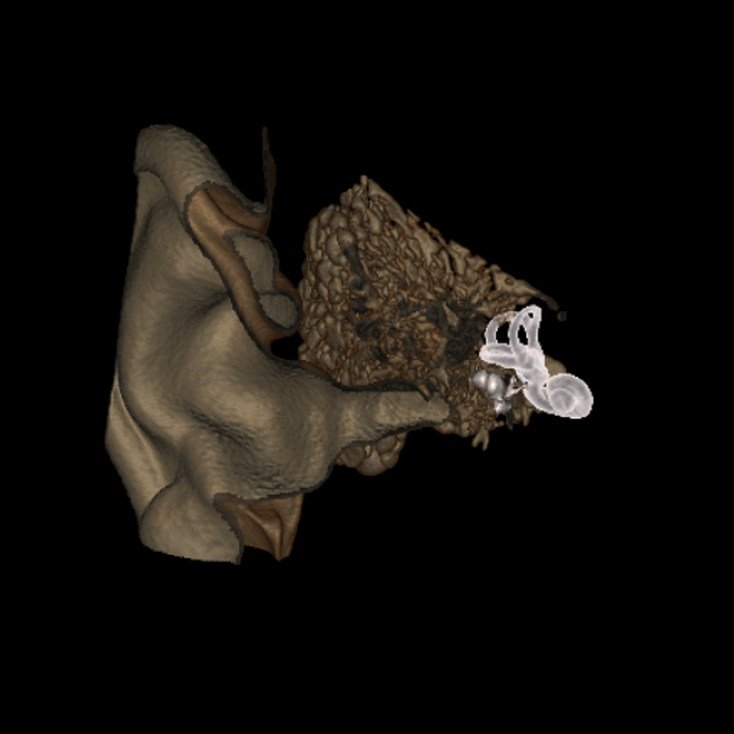

CT Scan Internal Ear